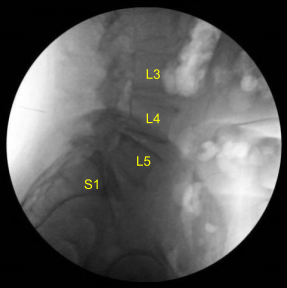

He was positioned prone on a Jackson Relton-Hall frame. All pressure points were carefully padded. They received preoperative prophylactic IV antibiotics, tranexamic acid and dexamethasone. Lumbar area was prepped with an electric hair clipper and cleaned with chlorhexidine. A 23-gauge spinal needle and fluoroscopy was used to localize the index level.

The C-arm unit, which was draped sterilely, was brought into the field and used to confirm the level. Neuronavigation array was affixed to the right superior posterior iliac crest with two Schanz pins after infiltrating with local anesthesia and making #15 blade stab incisions.

Post Op X-ray